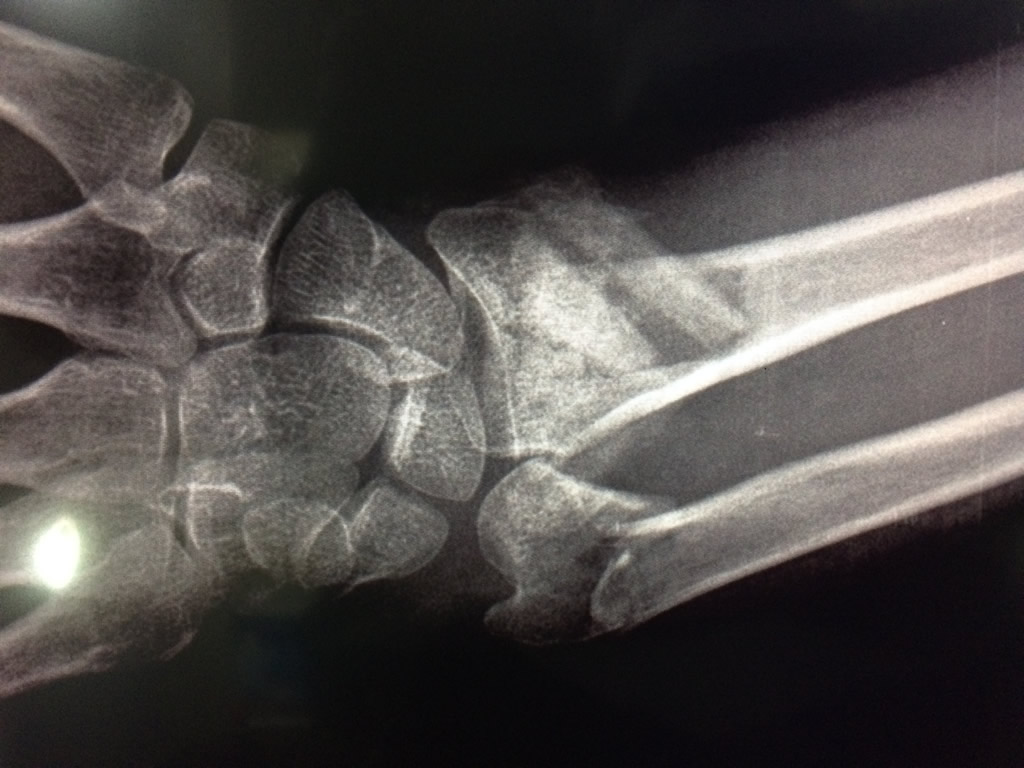

Cirugías de Húmero - Cirugías de Muñecas y Manos

Los procedimientos más comunes en cirugía de la mano son aquellos destinados a reparar traumatismos, incluyendo lesiones de tendones, nervios, vasos sanguíneos, y articulaciones; huesos fracturados; y quemaduras, cortes, y otros daños de la piel.